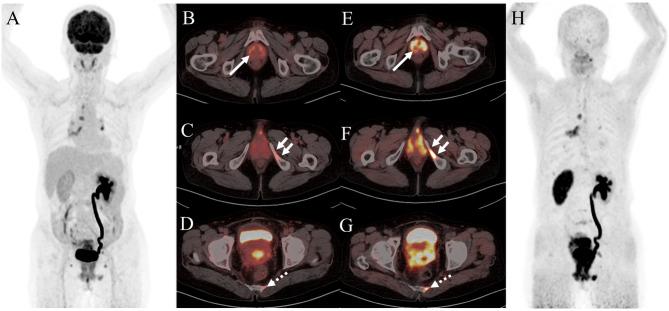

Ga-FAPI (fibroblast activation protein inhibitor) is a novel and highly promising radiotracer for PET/CT imaging. It has shown significant tumor uptake and high sensitivity in lesion detection across a range of cancer types. We aimed to compare the diagnostic value of Ga-FAPI and F-FDG PET/CT in common gynecological malignancies.

Thirty-five patients (median age, 57 years [interquartile range], 51-65 years) were evaluated. In treatment-naive patients (n = 27), Ga-FAPI PET/CT led to upstaging of the clinical TNM stage in five (19%) patients compared with F-FDG PET/CT. No significant difference in tracer uptake was observed between F-FDG and Ga-FAPI for primary lesions: breast cancer (7.2 vs. 4.9, P = 0.086), ovarian cancer (16.3 vs. 15.7, P = 0.345), and cervical cancer (18.3 vs. 17.1, P = 0.703). For involved lymph nodes, Ga-FAPI PET/CT demonstrated a higher SUV for breast cancer (9.9 vs. 6.1, P = 0.007) and cervical cancer (6.3 vs. 4.8, P = 0.048), while no significant difference was noted for ovarian cancer (7.0 vs. 5.9, P = 0.179). Furthermore, Ga-FAPI PET/CT demonstrated higher specificity and accuracy compared to F-FDG PET/CT for detecting metastatic lymph nodes (100% vs. 66%, P < 0.001; 94% vs. 80%, P < 0.001). In contrast, sensitivity did not differ significantly (97% vs. 86%, P = 0.125). For most distant metastases, Ga-FAPI exhibited a higher SUV than F-FDG in bone metastases (12.9 vs. 4.9, P = 0.036).

Ga-FAPI PET/CT demonstrated higher tracer uptake and was superior to F-FDG PET/CT in detecting primary and metastatic lesions in patients with common gynecological malignancies.